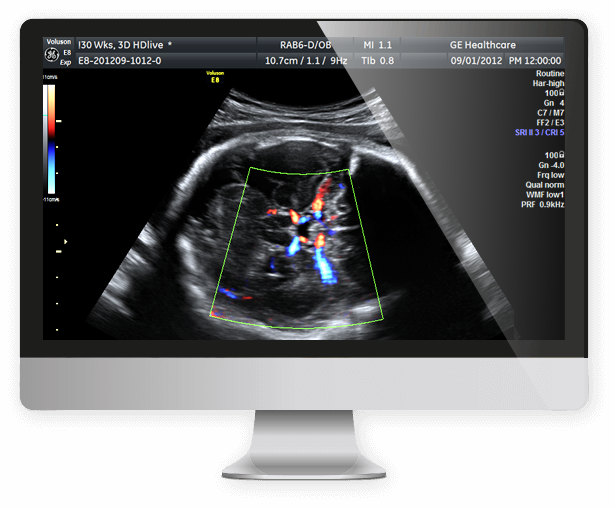

tecnologia

de ponta

Todos os exames são realizados em aparelhos de alta tecnologia e acompanhados pela Dra. Ana Lúcia Isotton, com 25 anos de experiência.